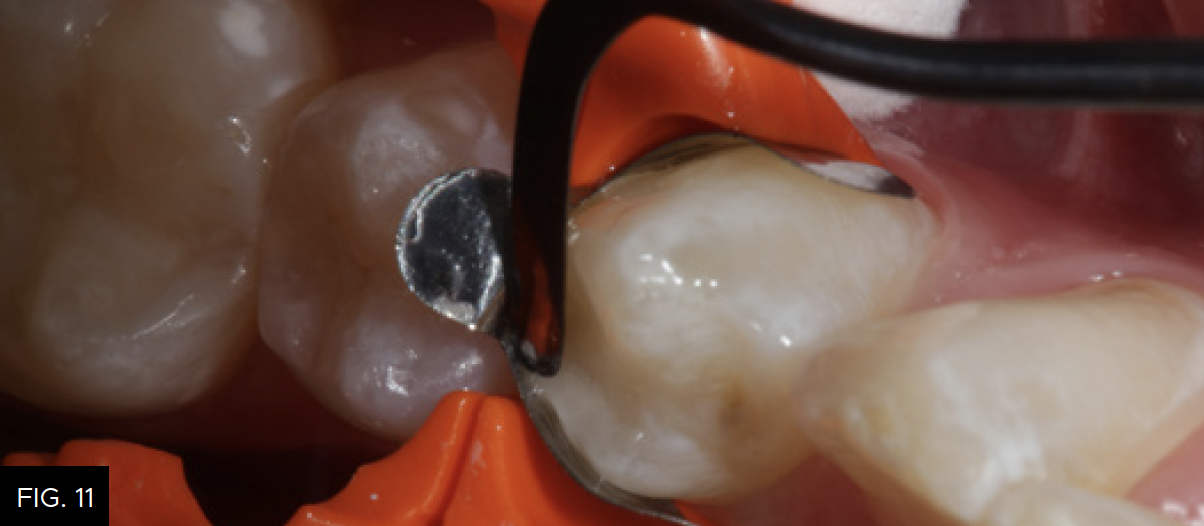

Using a unidose delivery, the first increment of composite resin (Evanesce, Clinician’s Choice) is placed into the proximal box of the preparation. A smooth ended composite placement instrument (Goldstein Flexithin Mini 4, HuFriedy) is used to adapt the restorative material to the inside of the sectional matrix and preparation. (FIG. 11)

The first increment of nano-enhanced composite (Evanesce, Clinician’s Choice) is placed using a composite placement instrument (Goldstein Flexithin Mini 4, HuFriedy).